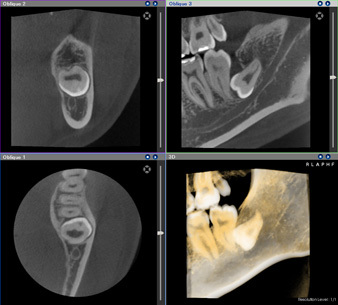

歯科用CTで三次元的に診断します。